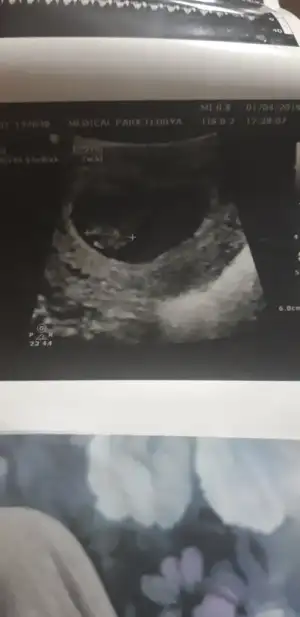

Hep güzel haberler alman dileğiyle .Kizlar medicalpark a gittimm bugun doktor cok iyi hastane cok temiz cok memnun kaldim . Orda devam edecegim. Bebek 7+ 3 muş.1 bucuk cm boyu henuzson adet tarihimi degistirdi 2 hafta geride cunku gec dollenme. Bu arada kesenin saginda duruor kiź olur derler bakalim dogru cikacak mi dedi

valla hangi tarafa yatik ben anlamiyorum sanirim

Ama benim de böyle sola yatıkEki Görüntüle 2253181 Eki Görüntüle 2253181 valla hangi tarafa yatik ben anlamiyorum sanirim

Ilk gebeligimde sol yumurtamda döllenme olmuştu.kizim oldu :)hatta buda sol yumurtdada döllenmiş bakalim merakla bekliyorum.Kizlar medicalpark a gittimm bugun doktor cok iyi hastane cok temiz cok memnun kaldim . Orda devam edecegim. Bebek 7+ 3 muş.1 bucuk cm boyu henuzson adet tarihimi degistirdi 2 hafta geride cunku gec dollenme. Bu arada kesenin saginda duruor kiź olur derler bakalim dogru cikacak mi dedi

Iste bende anlamadim bu isten bisey sagimi solumu karistirmaya basladim heralde dedimAma benim de böyle sola yatık

Bu usg karından ise bebek sagda yani erkek :)Eki Görüntüle 2253181 Eki Görüntüle 2253181 valla hangi tarafa yatik ben anlamiyorum sanirim